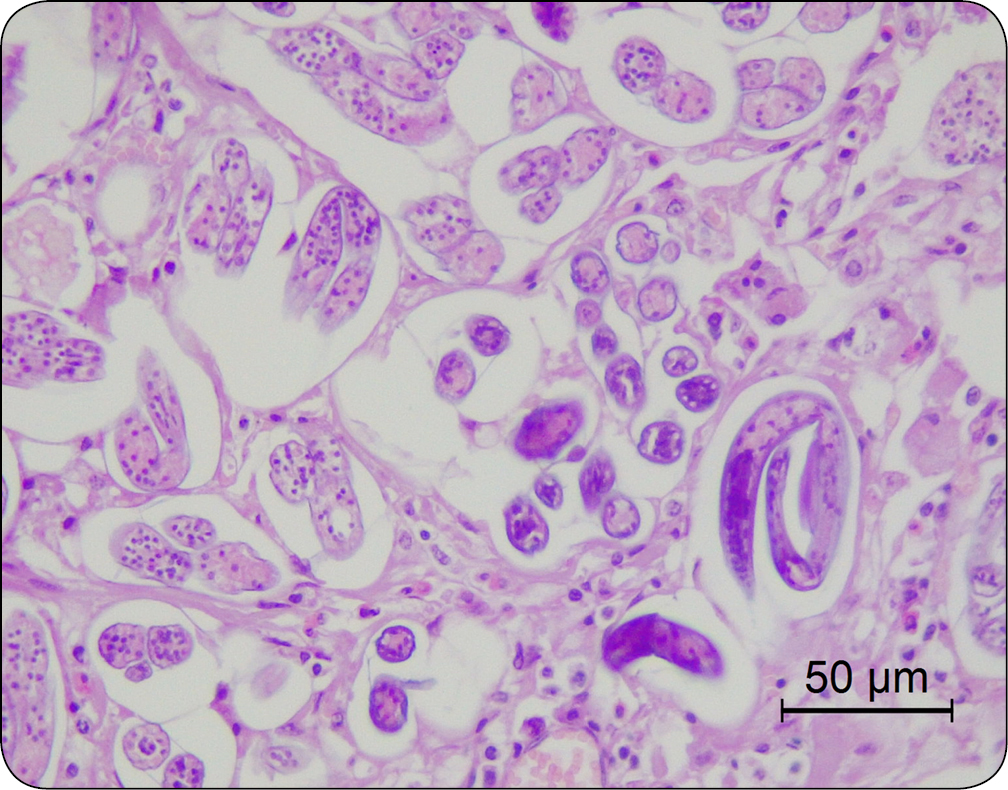

Nadciśnienie płucne może być wywołane zarówno obecnością pasożytów w prawej komorze serca i tętnicy płucnej (Dirofilaria immitis; ryc. 5), jak i w tkance płuc (nicienie płucne; ryc. 6). Ze względu na złożony mechanizm wywoływanych zmian infestacje pasożytnicze nie są zaliczane do typowo zapalnych przyczyn nadciśnienia płucnego (typ 3) (2). Obecność pasożytów może skutkować zapaleniem drobnych tętniczek płucnych, epizodami zatorowo-zakrzepowymi, a także cechami zapalenia płuc (2). Ten typ nadciśnienia płucnego jest wyjątkowy w medycynie weterynaryjnej, jako że ludzie nie są narażeni na rozwój PH w efekcie obecności Dirofilaria immitis czy Angiostrongylus sp. (2).